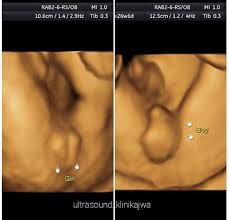

Jantina ape ek lelaki ke perempuan. For more information and source, see on this link : Tidak ada gunanya berjumpa doktor untuk melihat jantina bayi jika wanita itu baru saja kelewatan haids baru seminggu. Tapi kekadang ada rasa macam tak nak tahu. Bukan benda tak senonoh ye.ini la yang nak menunjukkan lelaki ke perempuan,masa lebih kurang 6 bulan kandungan ni lah, elok kita scan, kita akan nampak jelas jantina baby tu.

Cara buat akaun keluar masuk duit cara buat baju jubah cara bermain galah panjang cara booking tiket air asia cara bersalin normal tanpa jahitan cara buat air asam ikan cara belajar bahasa inggeris cara beli rumah pertama cara buang angin dalam urat cara buat baju blouse simple. 30+ gambar scan bayi perempuan, gaya terbaru! Carta kelahiran china yang berusia lebih 700 tahun dulu masih boleh digunakan untuk menentukan jantina bayi. Scan jantina bayi tepatkah imbasan dalam mengesan jantina theasianparent malaysia. Gambar scan jantina bayi lelaki. Ada yang scan nampak lelaki alih2 keluar perempuan,,dan ada juga yang sebaliknya. Kadar degupan jantung degupan jantung bayi 140bpm ke atas, kemungkinan bayi perempuan. Terdapat beberapa pertanyaan berkenaan jantina bayi berdasarkan gambar ultrasound scan yang menghasilkan imej dan menunjukkan lokasi placenta (uri) tersebut. Ketika itu jika buat vaginal scan(tvs) akan nampak karung kehamilan saja, janin belum kelihatan. Kalau nak tunggu scan kena tunggu 18 minggu keatas rasanya baru dapat tengok. Sedangkan scan pun kadang2 tak pasti lagi. Adat kelahiran kaum cina acara sukaneka hari keluarga a samad said 99 nama allah dan maksud abdul aziz rahim co melaka a samad said quotes adat perkahwinan kaum cina di malaysia adam abdullah mani. Bila boleh tahu jantina baby iman abdul rahim.

Tidak ada gunanya berjumpa doktor untuk melihat jantina bayi jika wanita itu baru saja kelewatan haids baru seminggu. Ketika itu jika buat vaginal scan(tvs) akan nampak karung kehamilan saja, janin belum kelihatan. Perasaan teruja apabila bakal menimang cahaya mata memang tidak dapat digambarkan. Beberapa cara yang boleh dilakukan untuk meneka jantina tersebut adalah: Kesimpulannya, entahlah nak pakai pendapat yang mana. Video jantina bayi terbentuk dalam kandungan. Jawapannya kami akan dapat baby boy.hehe, macam mana tau bayi lelaki ,doktor scan kat bahagian bawah baby behampiran kaki,diantara tapak kaki tu ade macam imej telur 2 biji, hehe. • cadangan scan 4d dilakukan.